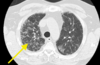

- Estudio - Patrón

- TC - Nodular